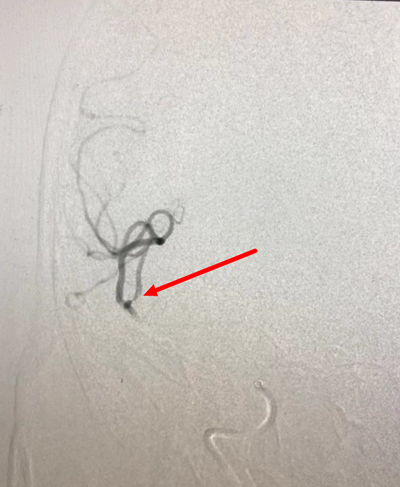

病例1:

DSA显示右侧M2下干闭塞

微导管造影显示真腔

取栓后血管再通